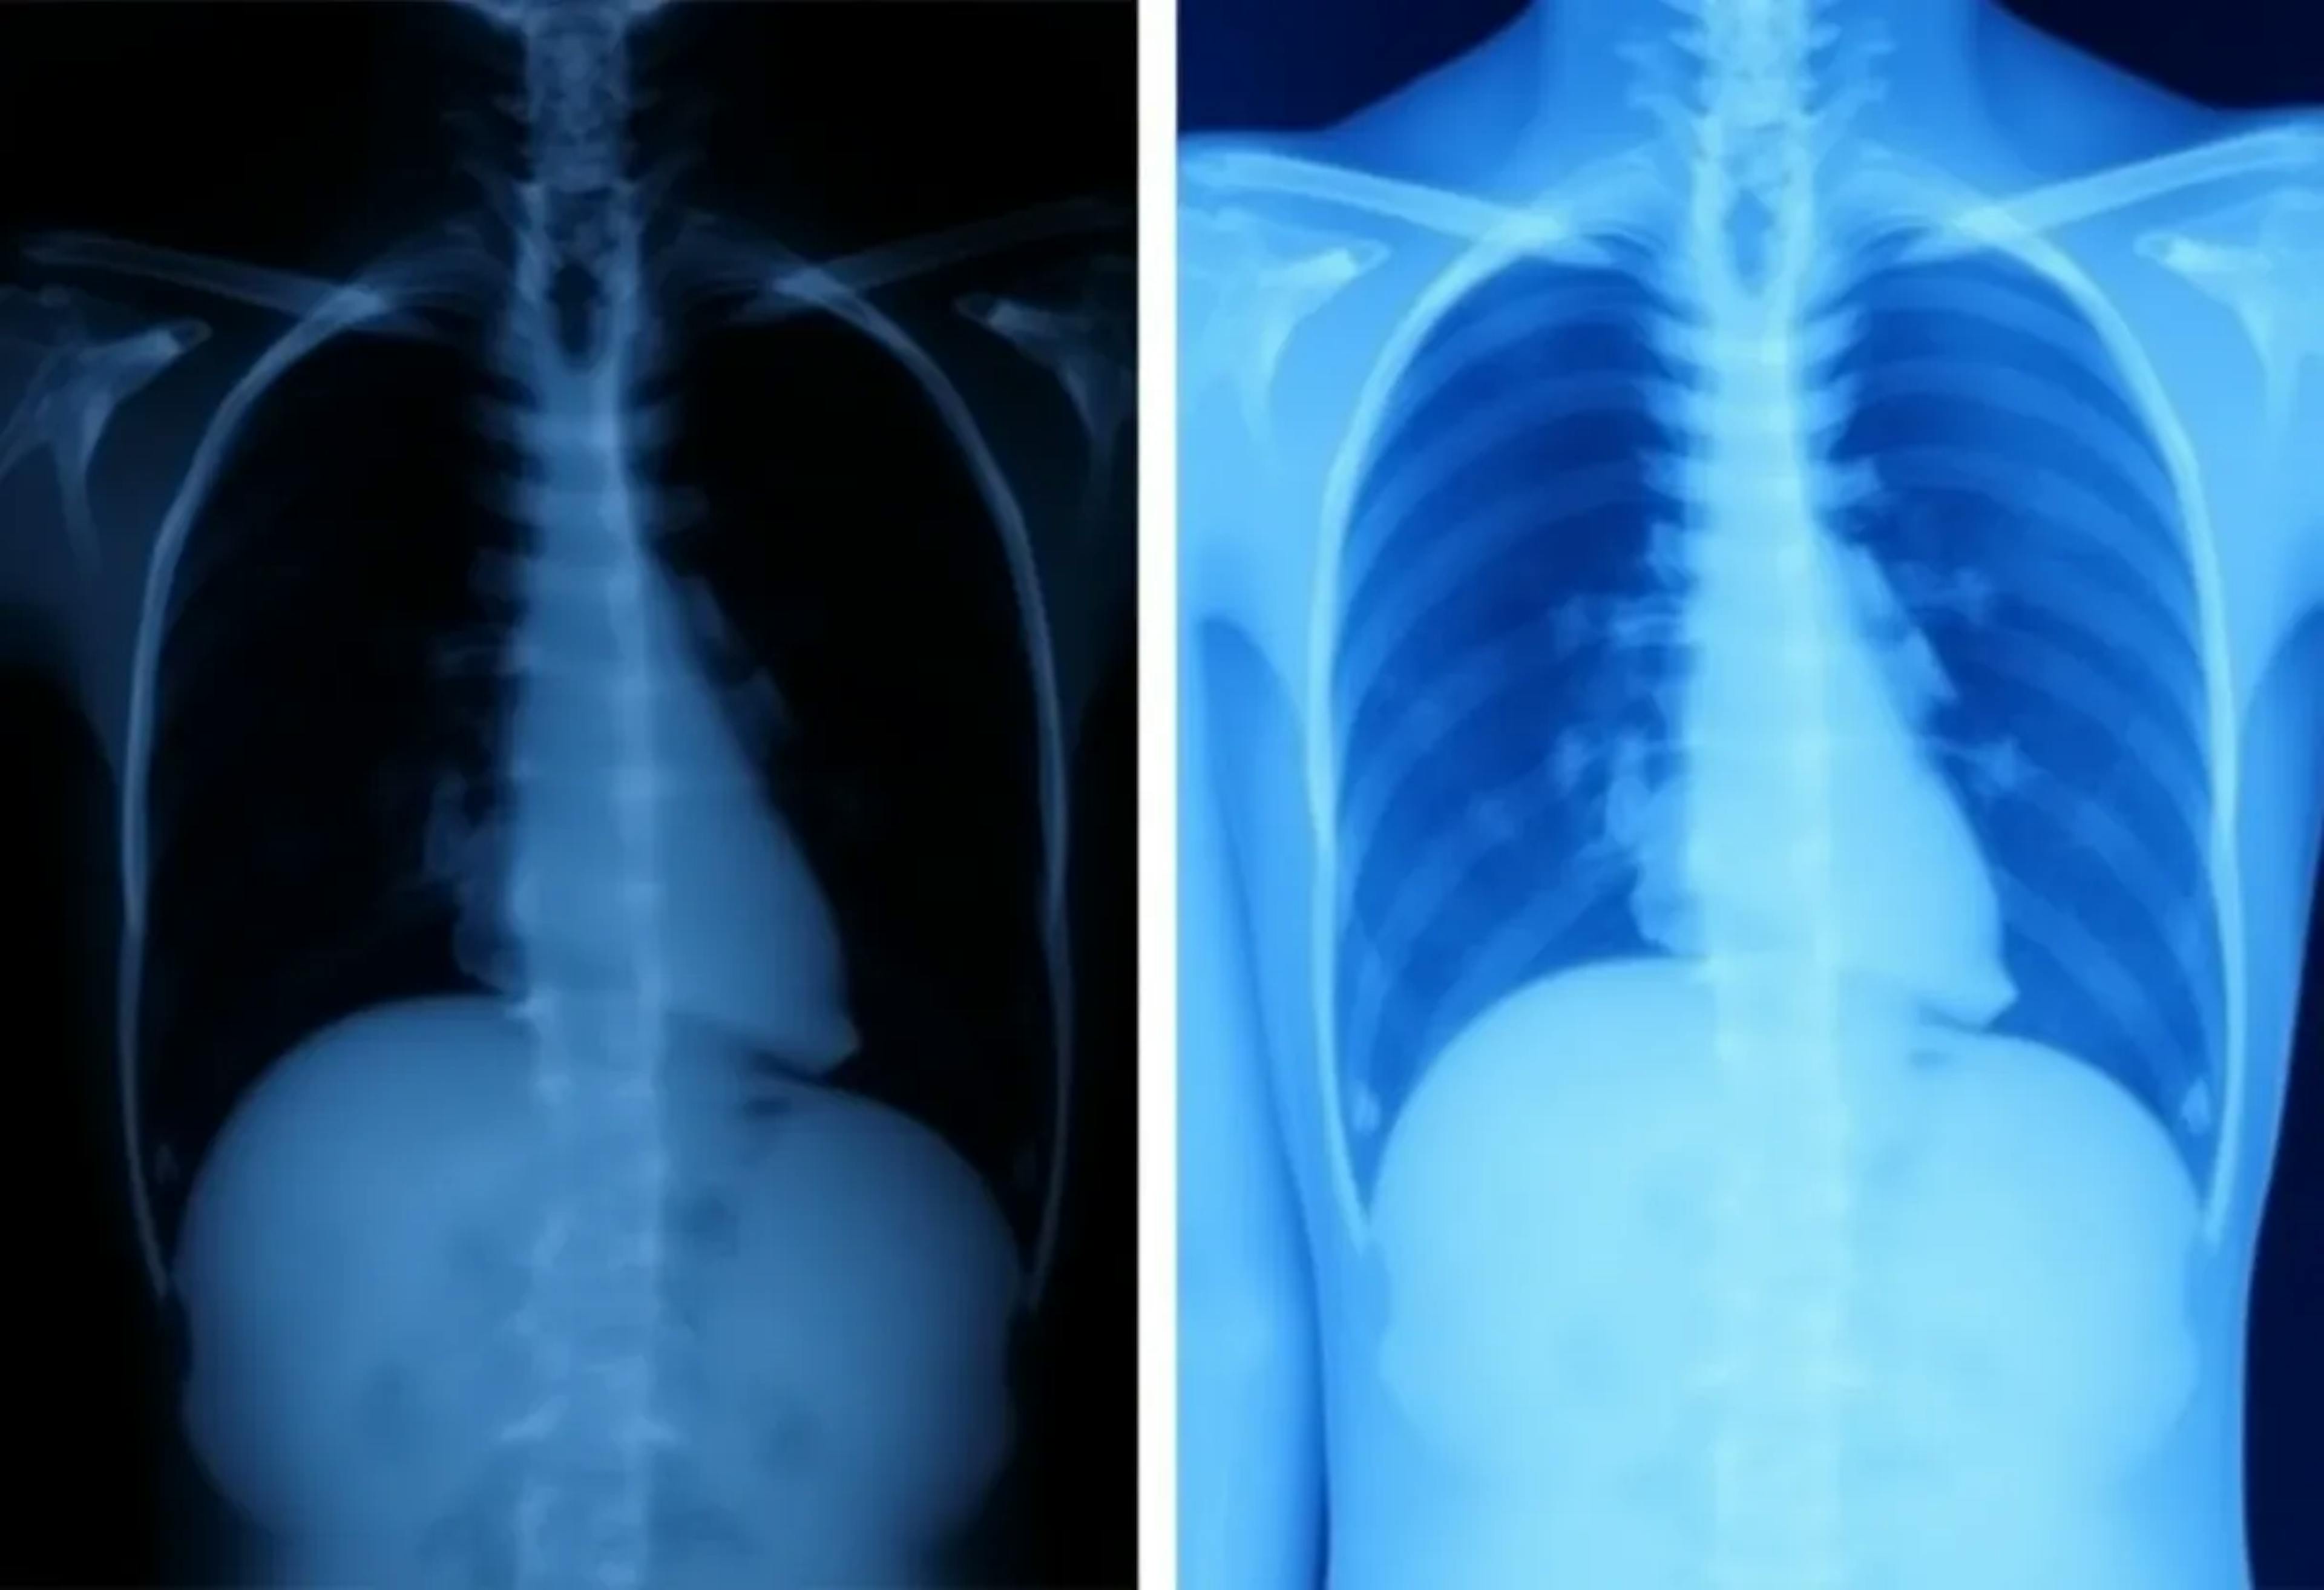

New Study Shows How Positive-Sum Fairness Impacts Medical AI Models in Chest Radiography